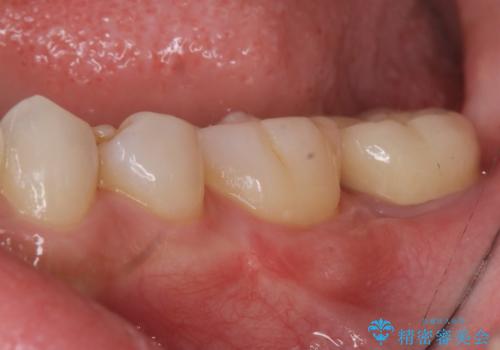

4:歯ぐきが少し落ち着いたところで仮歯にする

5:手術から5ヶ月待って、最終形成を行う

6:歯型をとり、クラウンを作成、仮着する

7:色、形、咬みごこち等問題なければクラウンを本セットする